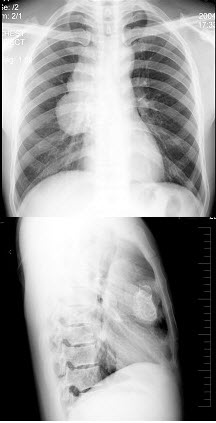

24、单项选择题

男,22岁,感胸痛且大汗淋漓就诊,X线检查如图,最可能的诊断是()

D.放射状粘膜纠集

男,1岁零8个月,生长发育差,易患呼吸道感染,心悸气促,心脏正、侧位片检查如图所示,正确的描述和诊断是()

A.正位示心影向两侧扩大,心尖左移

B.肺纹理增多

C.侧位示心前间隙变窄,心后食管前三角间隙消失

D.房间隔缺损

E.室间隔缺损